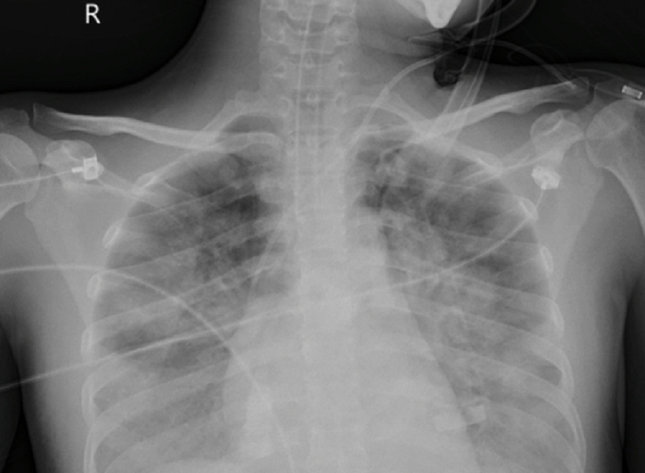

Phổi của nữ bệnh nhân bị tổn thương rất nặng cả hai bên phổi do nhiễm 'vi khuẩn ăn thịt người'

Tại đây, bệnh nhân được hồi sức chuyên sâu. Qua thăm khám, chẩn đoán hình ảnh, các bác sĩ phát hiện người bệnh bị tổn thương phổi lan tỏa hai bên chiếm gần 70% thể tích cả hai phổi. Người bệnh đã được đặt hệ thống oxy hóa qua màng ngoài cơ thể (VV-ECMO).